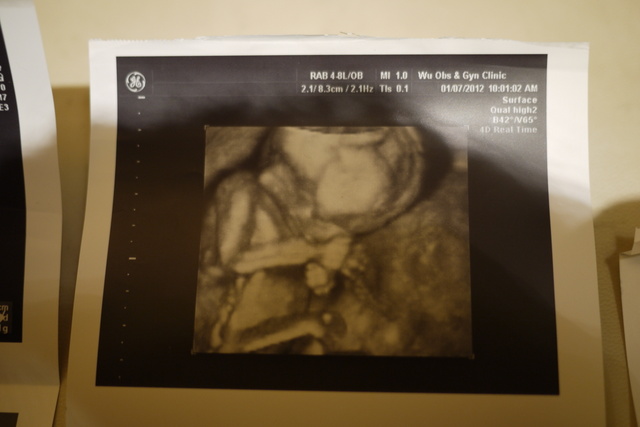

超音波照片有包括2D和3D的......

有部的特 ( 部特都是3D超音波 ).....有心、心跳、部、腿部的特....

3D立影可以看出小果的手!!!!!

五官越越清楚......手放在旁.....睡得很香甜~~~~

依然是部特.....她真的很把手放在旁呢~~~~